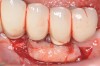

Dental implants have revolutionized the way in which clinicians treat and restore partially and fully edentulous patients and have demonstrated success for managing a broad range of clinical dilemmas. While implants have been highly predictable and have achieved long-term success, they are not immune from complications associated with improper treatment planning, poor surgical and prosthetic execution, material failure, and inadequate or infrequent maintenance. Among these problems are the biologic complications of peri-implant mucositis and peri-implantitis, which are inflammatory conditions in the soft and/or hard tissues surrounding dental implants (Figure 1 through Figure 4).1,2

Fig 3. The implants were treated with a Nd:YAG laser. A thrombogenic clot was present at the completion of this treatment.

Figure 3

Fig 4. Clinical view of the area 3 months post-therapy. Shallow probings of 3 mm were present around the dental implants with absence of bleeding. However, the mucogingival deformities remained on the premolar implants and would require treatment.

Figure 4